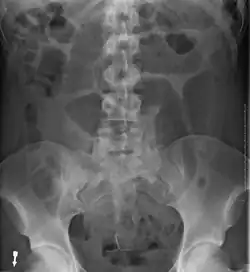

- Abdominal x-ray – tire-like shadow arising from the right iliac fossa and passing to the left

An x-ray of a person with a small bowel volvulus.

Plain X ray of a cecal volvulus -